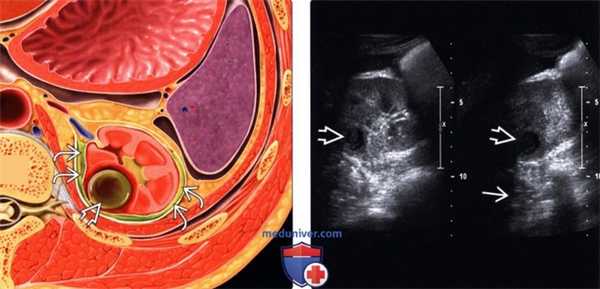

(Левый) На рисунке показана заполненная гноем полость в паренхиме почки и гнойное содержимое в околопочечном пространстве.

(Правый) На поперечном и продольном срезах визуализируется гипоэхогенное образование с четкими контурами в заднем отделе правой почки. Обратите внимание на заднее акустическое усиление.